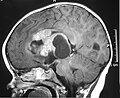

Atypical teratoid/rhabdoid tumour, abbreviated AT/RT, is malignant tumour usually found supratentorially.

- Usually supratentorial, occasionally in posterior fossa, case reports of spinal cord.

| Site | CNS - typically supratentorial |